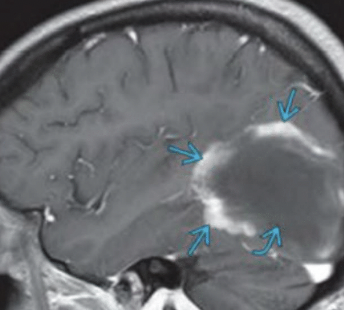

Imagen

RM

DEDOS DE DAWSON

HIPERINTENSIDADES CALLOSEPTALES EN T2 Y FLAIR